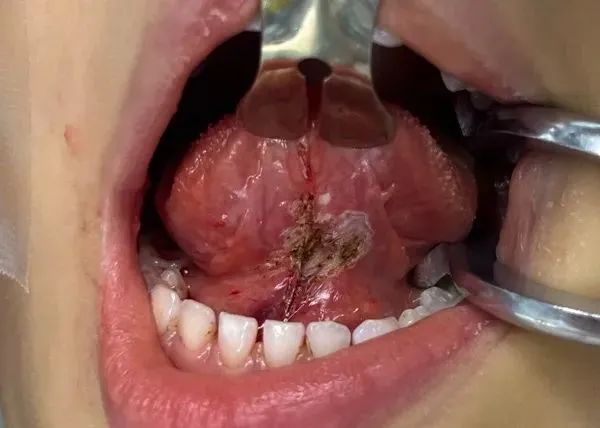

医院是中华医学会激光医学专委会副主委单位,在激光治疗口腔疾病方面有丰富的经验。相比传统手术方法,使用激光技术进行系带修整(如舌系带、唇系带过短的矫正)优势显著:

1)创伤小,出血少:激光的高能量可瞬间切割并封闭小血管,术中几乎不出血,无需缝合,减少了组织损伤和术后血肿的风险;

2)疼痛轻,恢复快:激光对周围组织的热损伤范围小,术后炎症反应轻,患者疼痛感明显低于传统手术,恢复期通常更短,能更快恢复正常饮食和活动;

3)精度高,视野清晰:激光能量集中,可精准切割目标组织,不影响周围健康组织;且术中无出血干扰,医生视野更清晰,操作更精准;

4)感染风险低:激光的高温有一定杀菌作用,能减少手术区域的细菌数量,降低术后感染的可能性。